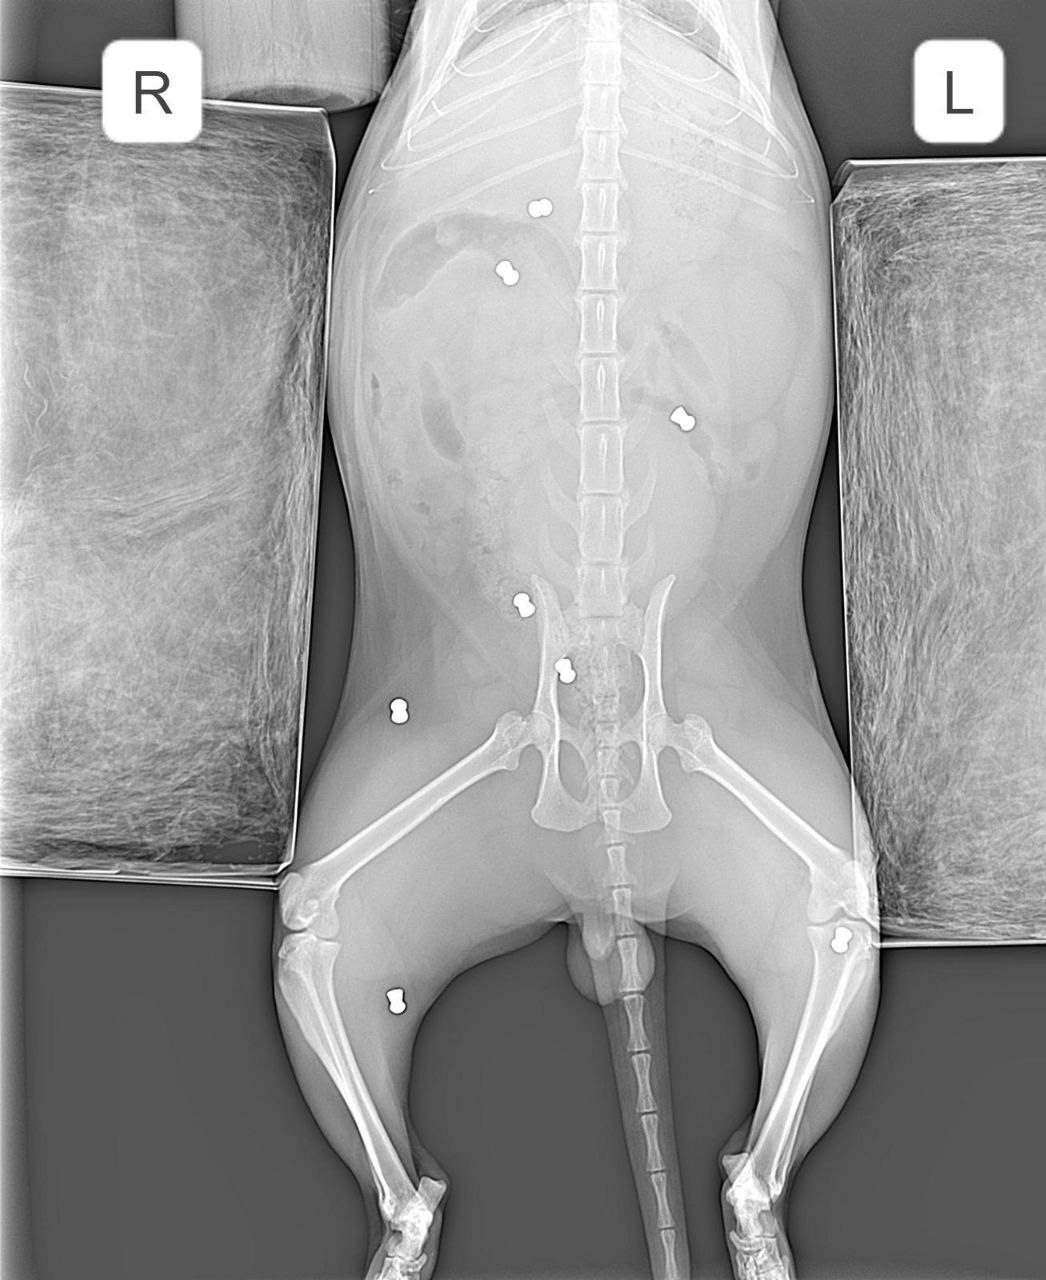

В Арзамасе неизвестный расстрелял кота из «воздушки». Кот ушёл гулять, а вернулся со множеством пуль по всему телу.

Ветеринар заключил, что пушистика привязали, чтобы он не убегал, и стреляли в него. Бедняга сейчас в больнице в тяжёлом состоянии.